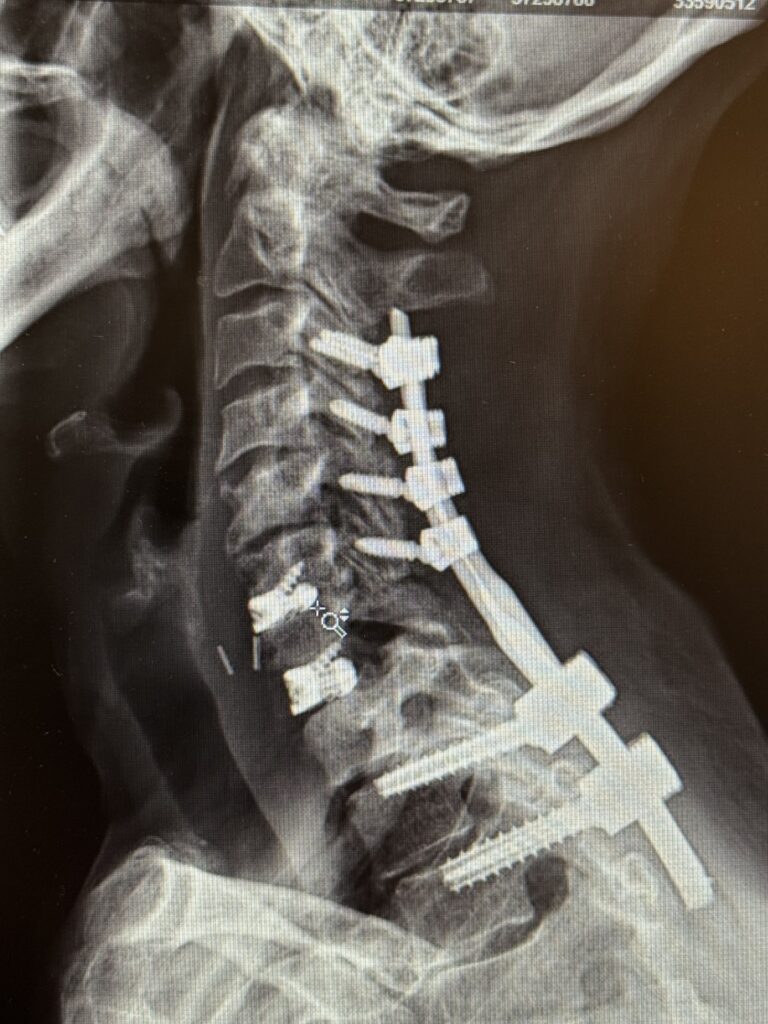

REVISION SURGERY TREATS INTRACTABLE NECK PAIN & CERVICAL DEFORMITY Clinical Presentation The patient is a 61-year-old female with a history of rheumatoid arthritis. She is 2-1/2-years […]